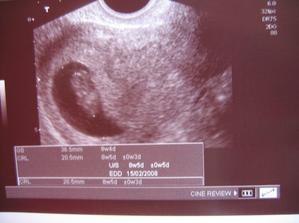

Malý uhlíček🙂

Měli jsme svatbu 25.srpna a na konci června jsme zjistili,že se mi něco vyklubalo v bříšku🙂No a vzhledem k tomu,že jsem si svatební šaty vybírala v lednu ještě bez mimíska tak jsem se obávala jestli se do nich vůbec vejdu,ale mimísek jako by to tušil a začal se víc ukazovat až na svatební cestě🙂A ted už jen rosteme a rosteme🙂